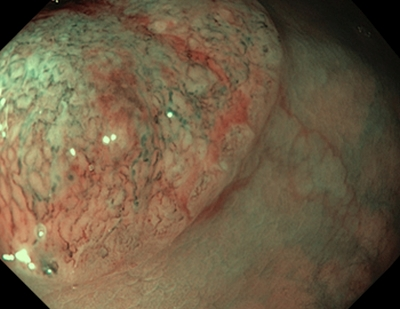

Тип 3 — характерний для злоякісної пухлини (ЗМ)

Колір: темніший за навколишнє, коричневий, іноді зі світлішими плямами

Судини: ділянки з перерваними або відсутніми судинами

Поверхня: аморфна або без малюнка на поверхні